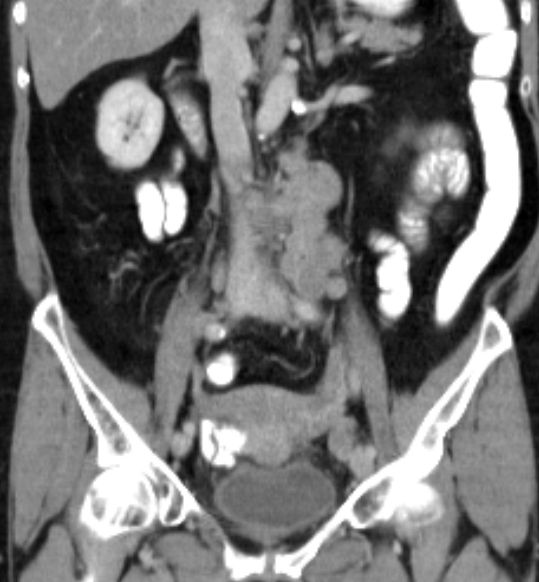

| paraaortale Lymphknoten - Metastasen |

![]() Großes Lymphknotenkonglomerat links paraaortal. Vergrößerte Lymphknoten an der linken Beckenwand. |

![]() 2 große Lymphknoten links zwischen Aorta und Musculus psoas. | ||